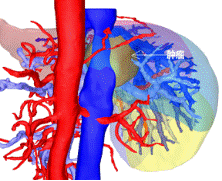

通過CT、磁共振以及三維重建的圖像來看,王先生的腫瘤位于肝臟尾狀葉,除左側(cè)可見少量肝組織以外,腫瘤已侵犯絕大部分的尾狀葉!“跟土豆差不多大!”胡偉表示,王先生的肝臟腫瘤約有5*5*4㎝大小,手術(shù)切除對(duì)于他來說是目前唯一有效的治療方案!

術(shù)前增強(qiáng)CT顯示腫瘤位于肝臟尾狀葉

3D顯示被血管包繞的腫瘤